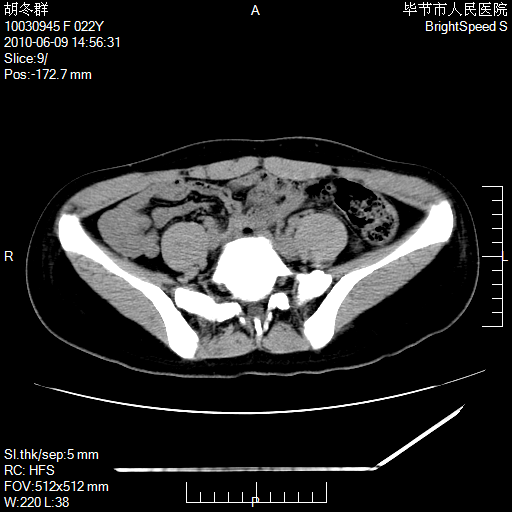

患者23岁,发现腹部包块3月。

盆腔内囊性占位;穿刺或者直接手术拿掉即可,不必紧张。

左侧卵巢囊腺瘤或囊腺癌

盆腔内囊性占位性病变;考虑左侧卵巢囊腺瘤。

有分隔、壁薄,支持考虑左侧卵巢囊腺瘤。

左侧卵巢浆液性囊腺瘤。

支持考虑左侧卵巢囊腺瘤;宫腔积液。

有分隔、壁薄,支持考虑左侧卵巢囊腺瘤。排尿后,膀胱缩小,由于重力作用,肿块下移就到了膀胱位置,很好理解。